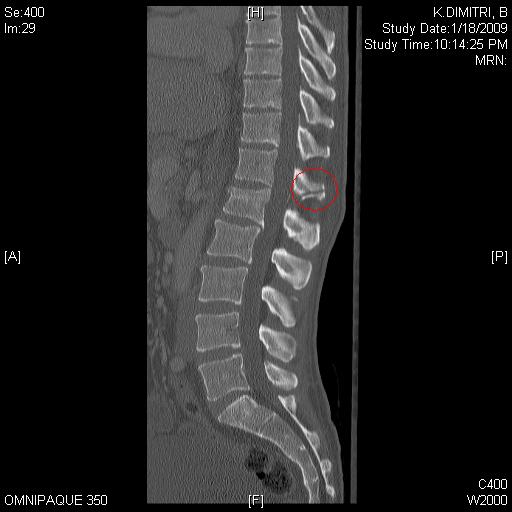

Jan 2009 vertebral column fracture